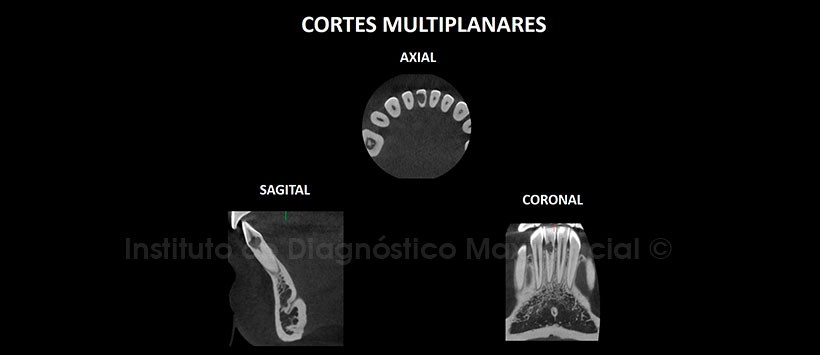

A la evaluación de la radiografía Panorámica (Figura 1) se apreció una imagen radiolúcida de contorno irregular en el tercio cervical de la pieza 41 además de falta de definición del conducto radicular en el tercio medio y apical. A la evaluación de la tomografía computarizada Cone beam mediante cortes axiales, coronales, sagitales (Figuras 2 y 3) y transaxiales (Figura 4), se encontró la presencia de una imagen hipodensa de contorno irregular en el tercio cervical en relación al conducto radicular, que muestra una marcada extensión ocasionando la erosión de la superficie radicular en la zona cérvico distal condicionando comunicación con el espacio periodontal. Signos tomográficos de proceso de reabsorción radicular interna.

Se evidenció, así también, obliteración del conducto radicular en el tercio medio y apical. Probable relación a secuela post traumática.